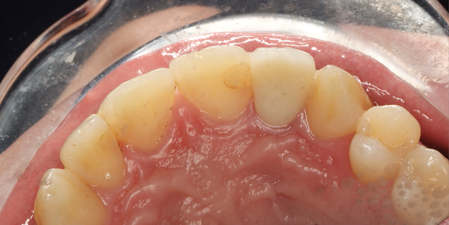

1/16/2025: All-ceramic crown restoration for #12; patient asymptomatic

The CBCT scans demonstrate the resolution process of periapical inflammation in tooth 12. Over a period of more than four months, the periapical inflammation has essentially subsided, and bone regeneration has initiated in the regions with bone defects caused by the prior inflammation.